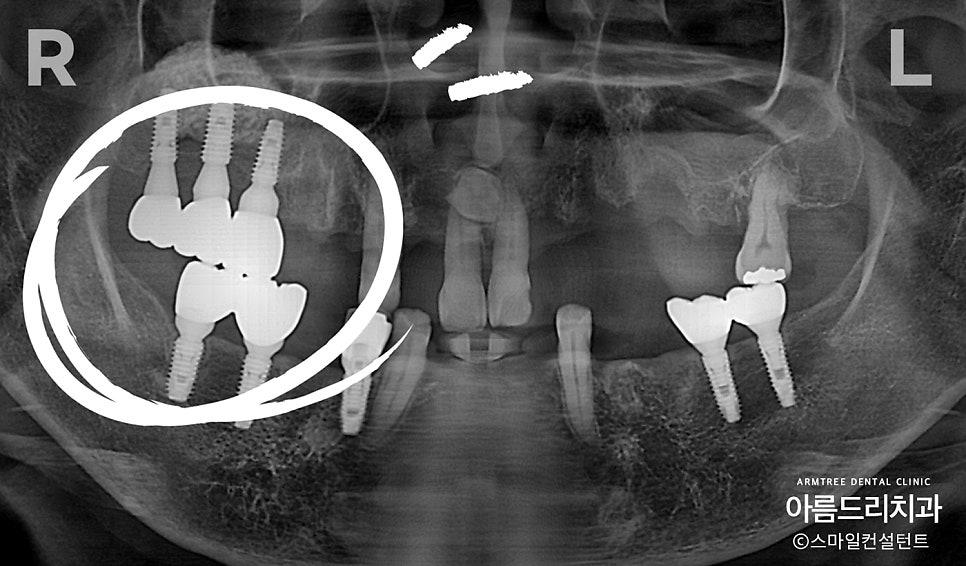

발치하지 않은 치아부분 뼈가 많이 튀어나와 있습니다.(파란색선)

반대로 발치된 곳은 뼈가 푹 꺼져있네요. (노란색선)

아래쪽도 발치한 곳은 뼈가 움푹 들어가 보입니다.

발치를 하면서 곧바로 임플란트를 심으면

오른쪽 위쪽과 아래쪽의

임플란트 위치를 잘못 계산한 결과입니다.

위에 맨 뒤 치아는 아래에 짝꿍이 없기

때문에 안 심어도 되는 상황입니다.

더군다나 위 아래 치아 맞물림을 맞춰놓지

않아 실제로 한 점만 씹히고 나머지 부분은

다 붕~ 떠 있는 상태였습니다.

밥이 잘 안 씹혔을텐데...,

환자분은 어태껏 잘 몰랐다고 하시네요.